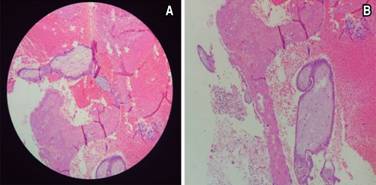

Se presentó al Servicio de Urgencias con los siguientes signos vitales: FC, 80 lpm; FR, 21 rpm; TA, 120/80; T, 37 oC; refería cuadro de dolor abdominal de aparición súbita con aproximadamente siete horas de evolución, constante, en la fosa iliaca derecha (FID), EVA 7/10, irradiado a la región lumbar ipsilateral, vómito en una ocasión de contenido gástrico, sin fiebre, acompañado de náusea y sangrado transvaginal de aproximadamente 15 cm3; negó ingesta previa de medicamentos, así como la presencia de exacerbantes y atenuantes. A la exploración, se encontró abdomen globoso a expensas de panículo adiposo, peristalsis presente, disminuida en la FID; abdomen blando, resistencia muscular voluntaria, doloroso a la palpación superficial, media y profunda en la FID; hiperbaralgesia e hiperestesia dudosas de predominio en la FID; no se palpó crecimiento uterino; dolor en punto de McBurney (+), VonBlumberg (+), Rovsing (-), talopercusión (+). Laboratorios de ingreso, con hemoglobina de 13.2, hematocrito de 38, leucocitos de 26.9, segmentado 95, BUN 10.2, urea 22.1, creatinina 0.58. El USG ginecológico reportó útero gestante de 12.0 × 8.2 × 7.4 cm en sus ejes longitudinal, AP y transversal. En la cavidad endometrial se observaron dos sacos gestacionales de localización normal y apariencia viable, compatibles con embarazo gemelar intrauterino; fondo de saco de Douglas con líquido libre; fosa iliaca derecha en topografía del ciego, se observó asa de paredes levemente engrosadas y peristalsis ausente, líquido libre alrededor; no se pudo descartar proceso inflamatorio apendicular (Figura 1). Se programó apendicectomía laparoscópica; se halló hemoperitoneo de 250 cm3, salpinge derecha aumentada de tamaño, rota y con sangrado activo compatible con embarazo ectópico roto, coágulo organizado en la FID; útero grávido aumentado de tamaño, anexo izquierdo normal, ovario derecho con cuerpo lúteo. Se realizó salpingectomía derecha, evacuación de hemoperitoneo y lavado de cavidad; se colocó drenaje tipo Blacke 19 French (Figura 2); postoperatorio con diagnóstico de embarazo heterotópico roto derecho (Figura 3). La paciente pasó compensada a la Unidad de Cuidado Postoperatorio. Al día siguiente, drenaje con gasto de 85 cm3 serohemático; se realizó un USG obstétrico que reportó vitalidad y viabilidad de los productos fetales intrauterinos (Figura 4). Cuarenta y ocho horas posteriores al procedimiento quirúrgico, se retiró el drenaje y fue dada de alta por los Servicios de Ginecología y Cirugía General. El nacimiento de dos productos, uno del sexo masculino y otro femenino, se llevó a cabo a las 35 SDG mediante cesárea; la indicación de la misma fue preeclampsia desarrollada durante el embarazo. No se presentaron complicaciones durante el procedimiento.

Figura 3: (A) Vellosidades del primer trimestre dentro de la luz de la salpinge. (B) Vellosidades y decidua adheridas a la pared de la salpinge.